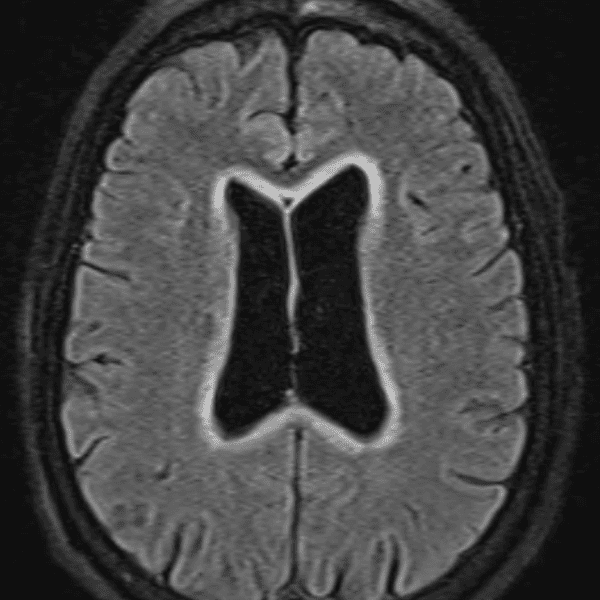

๋ฏธ๋ฌ˜ํ•˜๊ฑฐ๋‚˜ ์–ด๋ ค์šด ์‚ฌ๋ก€์™€ ์ผ๋ถ€ ์ •์ƒ ์‚ฌ๋ก€๋ฅผ ํฌํ•จํ•˜์—ฌ ๋‹น์ง์„ ์‹œ๋ฎฌ๋ ˆ์ด์…˜ํ•ฉ๋‹ˆ๋‹ค.

50 ์‚ฌ๋ก€